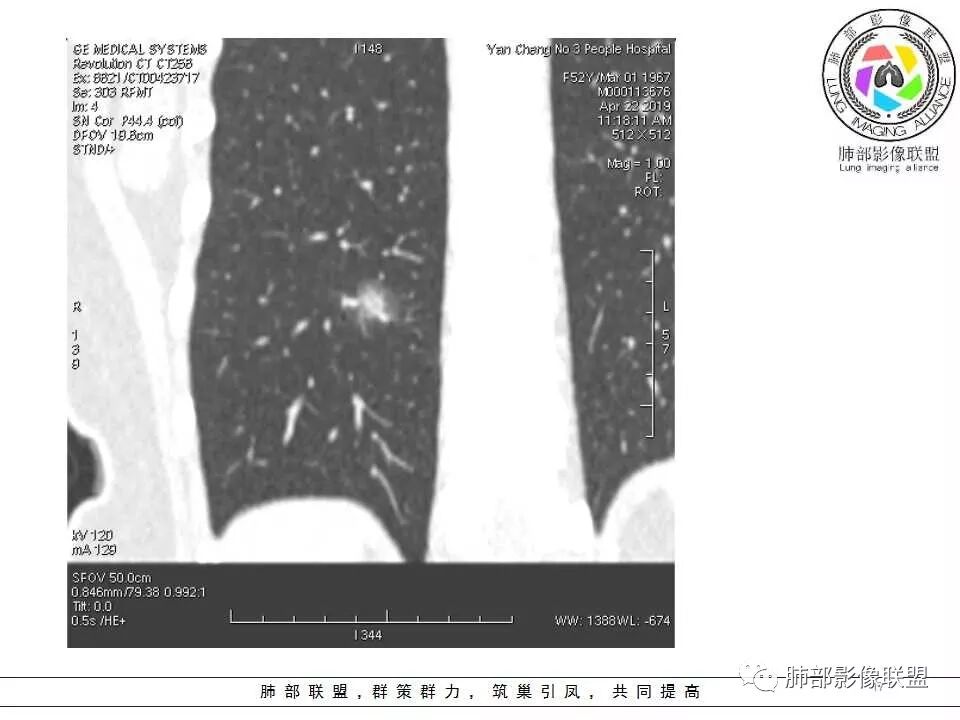

横断位看上去晕很模糊,冠矢状位重建后却比较清晰,所以单次CT检查蛮难定的,中心透亮区一定是空洞吗?我怎么觉得是一支气管壁有增厚,管腔有轻度扩张的支气管,第一感觉还是炎性结节吧,PC可能大,一定要否定腺癌也不敢,一个月左右复查。

体检发现肺部结节,右下肺混合密度结节,结节中心空泡,壁光滑,结节边缘模糊,血管在结节内增粗,矢状位前基底段还有一片磨玻璃影,所以考虑良性结节可能,炎性肉芽肿?抗炎后复查。腺癌合并炎性改变待排。

连续层面显示这个应该是空泡,或者小空洞,远端没有,近端也没有,周围环形软组织增厚。而空泡,影像上只是根据5mm界线,病理上不一定。

问一个问题,肺动脉肺静脉?为啥?

静脉,夹角90,周边没气管伴行。

静脉吧,动脉同时会伴有一根气管

这些呢?为啥?

动脉,有支气管伴行

伴有支气管

南边:

假如这是含气支气管,伴随的哪条动脉呢?近端从哪来?为啥环形壁增厚而又不均匀?都不太符合,所以支持空泡或小空洞。